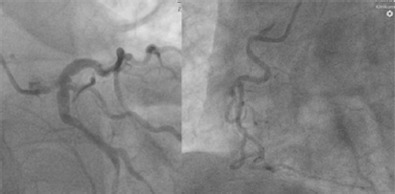

Drug-eluting stents (DES) are the gold standard for percutaneous coronary interventions (PCI); however, technical and anatomical challenges need to be addressed to ensure optimal apposition and prevent late adverse events. Complex vessel anatomies, including ectatic or aneurysmatic vessels, or significant differences in diameter in left main stenosis of the coronary artery, are clinical indications in which current PCI techniques attempt to shape conventional DES to follow vessel anatomy, thus modifying the original stent scaffold and its properties. However, due to their design, balloon-expandable cobalt-chromium and cobalt-nickel DES have limitations regarding their expansion capacity, which can result in undersizing and malapposition. New stent scaffolds have recently been introduced into clinical practice to address these challenging anatomies, including a drug-eluting nitinol stent platform. The nature of the nitinol device allows conformability to the native vessel, covering complex anatomies without manual adaptation. In this article, the authors present the rationale and current data on self-apposing nitinol DES in left main stenosis, and suggest that the device may be safely and effectively used with comparable rates of adverse cardiovascular events, as seen with second-generation balloon-expandable DES.